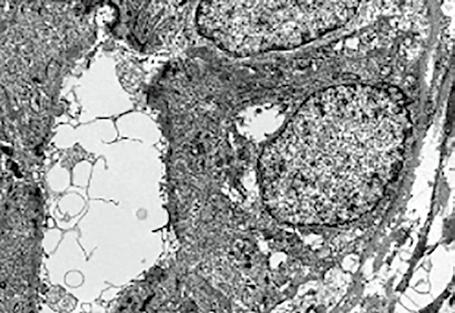

Bylo již uvedeno, že už dříve byl objeven jaterní lobulus, jehož koncepci detailně propracoval Kiernan v 19. století. Nové, soudobé pojetí lalůčku zavedl Rappaport, který rozdělil lalůček na tři zóny podle jejich vztahu k portálnímu prostoru. Jaterní architekturu objasnil v roce 1949 Elias. Podle jeho koncepce jsou játra složena z jednovrstevných buněčných plátů a trámců, které probíhají a ohýbají se ve všech směrech a vzájemně se prostupují tak, že vytvářejí nepravidelnou síť, která je prostoupena labyrintem lakun. Játra tak nabývají vzhledu mořské houby (obr. 1.13). Toto uspořádání je velice výhodné po stránce funkční. Elektronmikroskopické studie

Obr. 1.13 Houbovité uspořádání jaterní struktury (podle Eliase)

pak prokázaly vybavení hepatocytů různými organelami a umožnily i poznání vyvolávajících infekčních agens v jaterních buňkách.